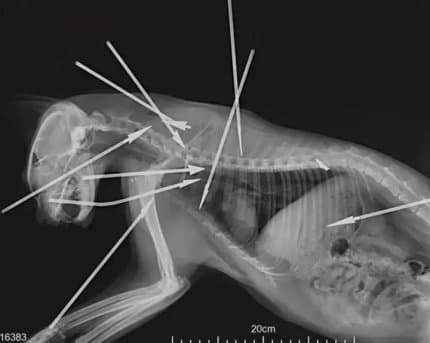

금속 다트 화살을 존나 던져서 대여섯 마리 죽임